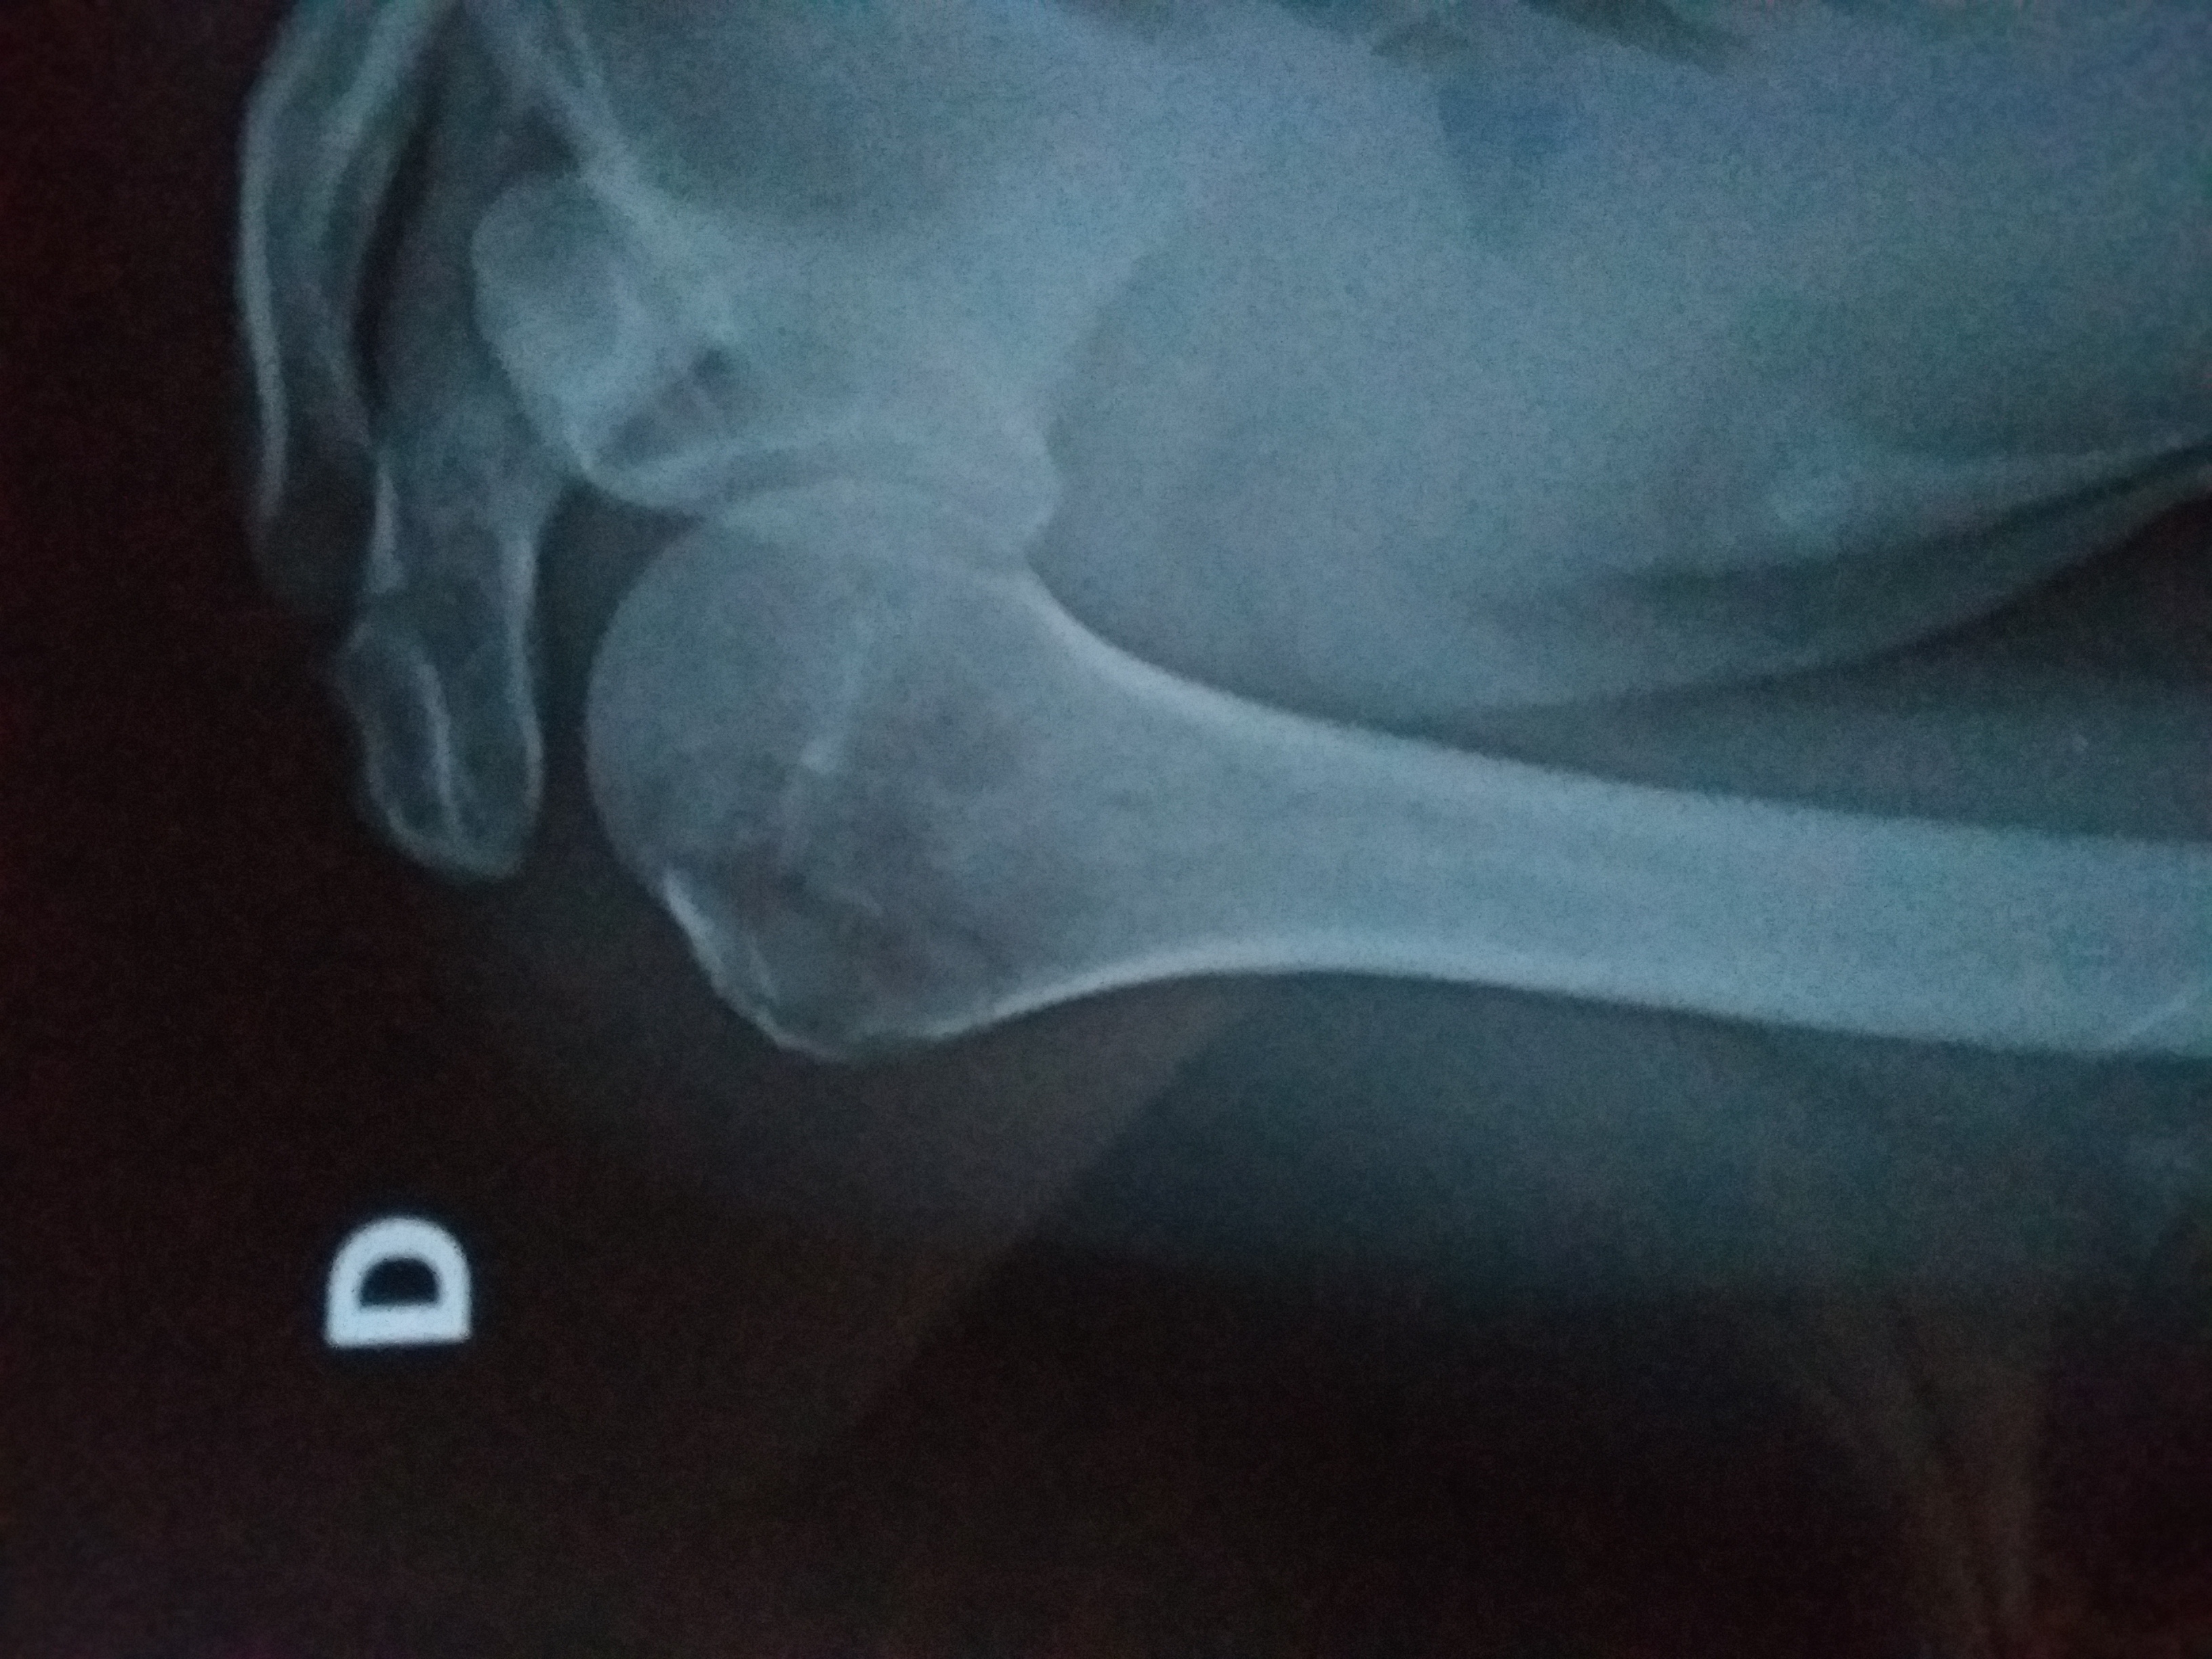

sono scivolato in casa e sono andato a sbattere contro il muro con la spalla.

Risultato frattura composta

in allegato la radiografia